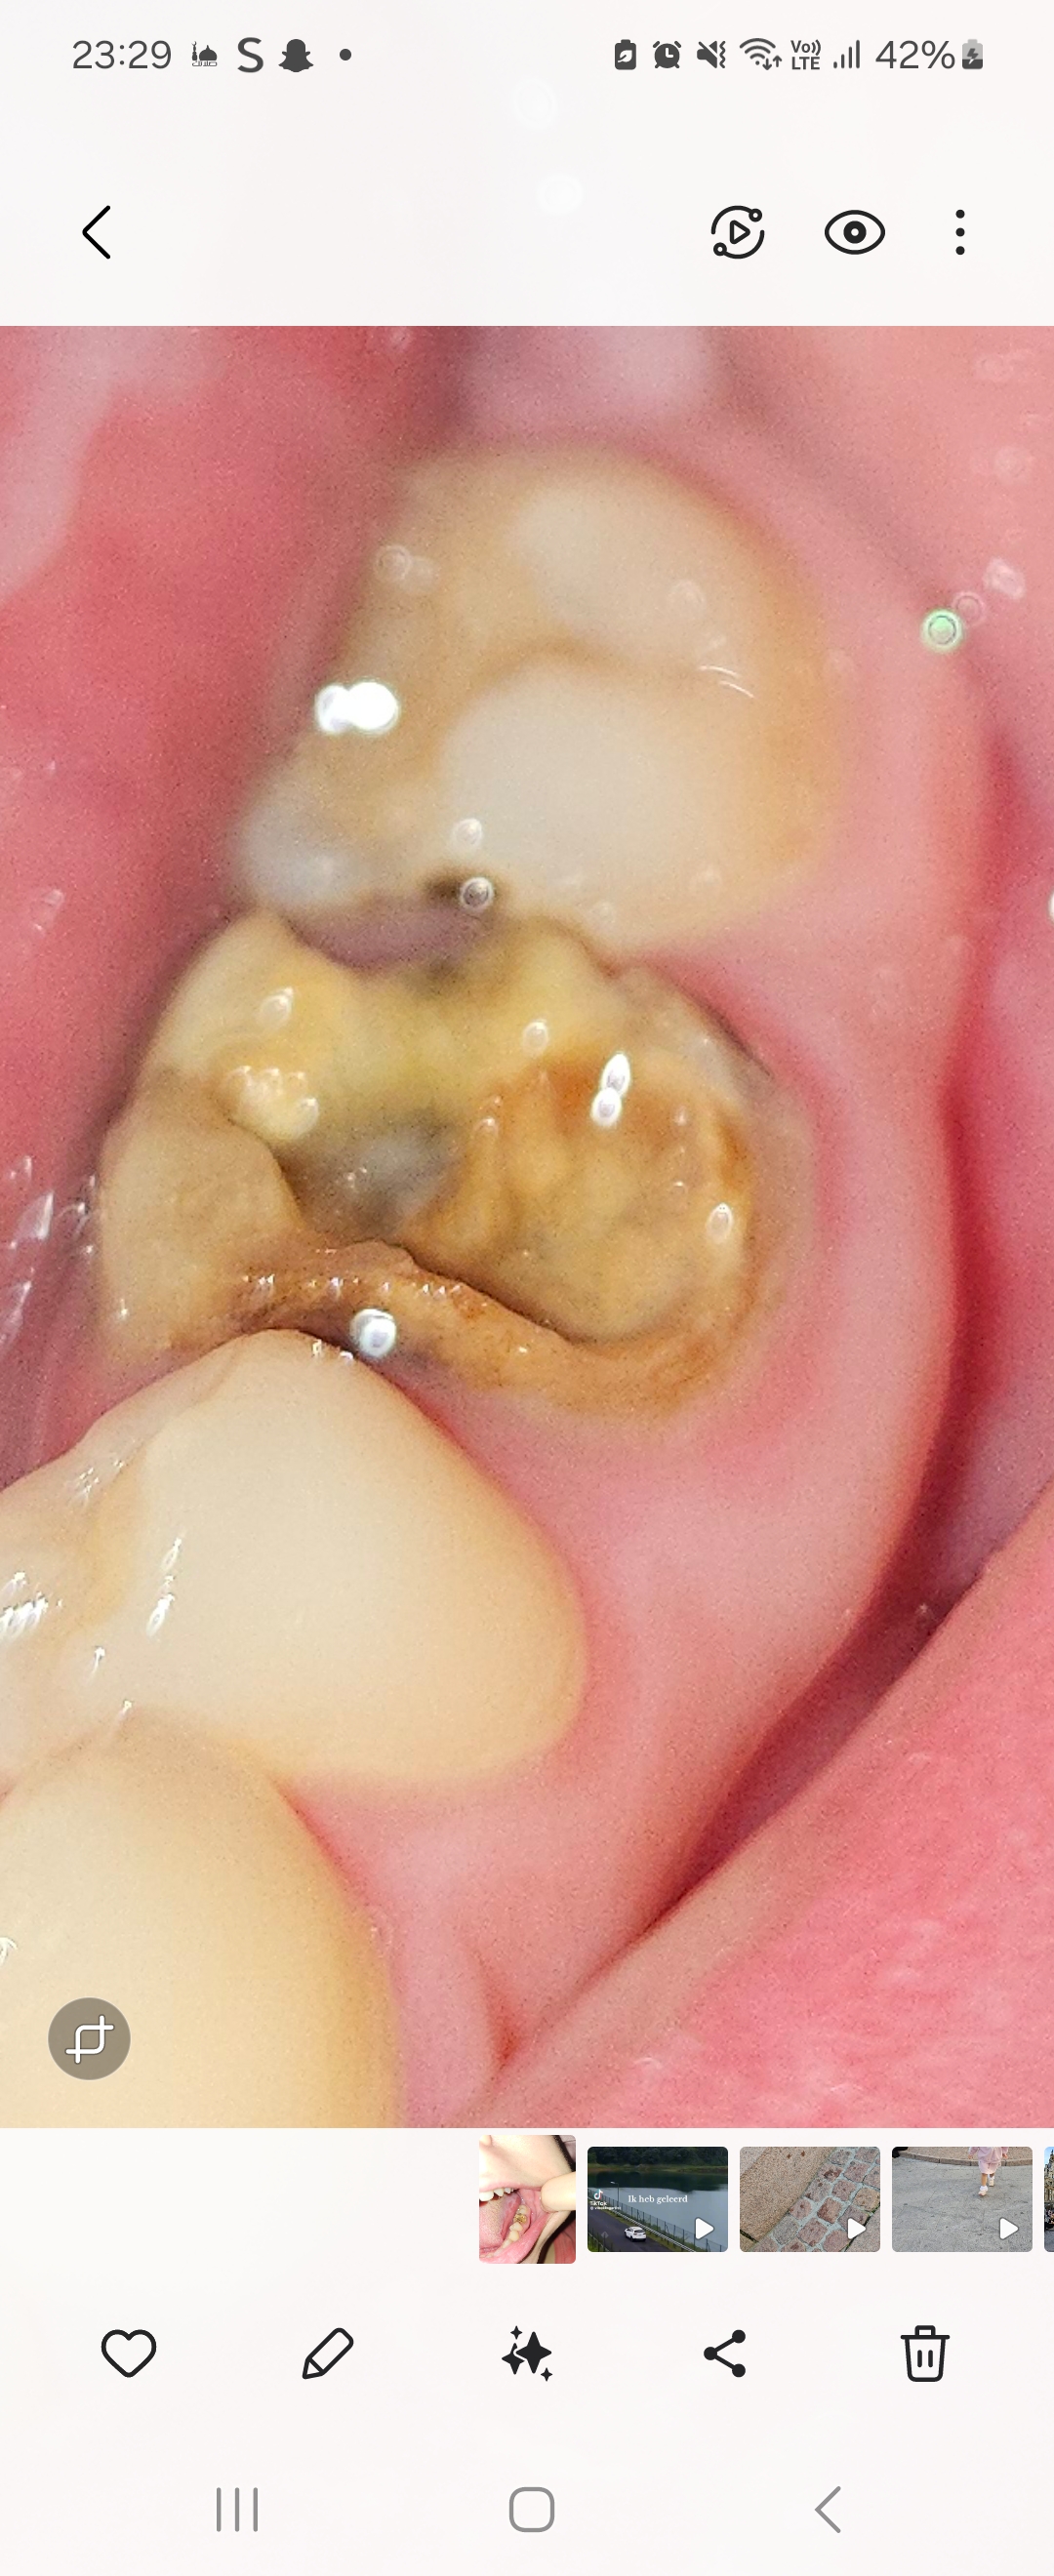

من ٢٠ سنة كنت مركبة ٤ تلبيسات ل ٤ ضروس ، من كم يوم سقطت تلبيسة وكان تحتها كتير مسوس ، هل لسا ممكن يتعالج ولا خلص ، وشوي صرت خايفة يكونو ال ٤ تلبيسات مسوس تحتهم لانو حولين التلبيسات منتفخ

1000111228 1000111226